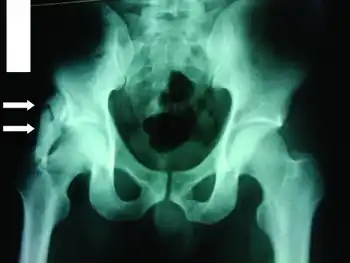

Most (i.e. 80%) ossifications arise in the thigh or arm, and are caused by a premature return to activity after an injury. Other sites include intercostal spaces, erector spinae, pectoralis muscles, glutei, and the chest. On planar x-ray, hazy densities are sometimes noted approximately one month after injury, while the denser opacities eventually seen may not be apparent until two months have passed.

Radiologic diagnosis

The radiological features of myositis ossificans are ‘faint soft tissue calcification within 2–6 weeks, (may have well-defined bony margins by 8 weeks) separated from periosteum by lucent zone and on CT, the characteristic feature is peripheral ossification’.[10][11][12]